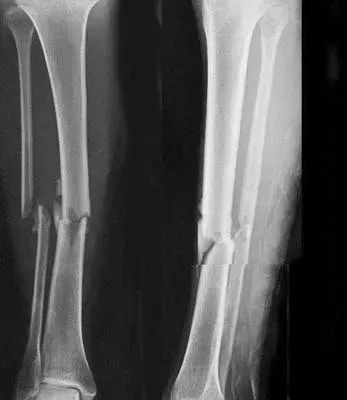

5、小腿踢球時骨折過,還能當兵嗎?

四肢單純性骨折,治愈1年后,X線片顯示骨折線消失,復位良好,無功能障礙及后遺癥(空降兵除外),合格。